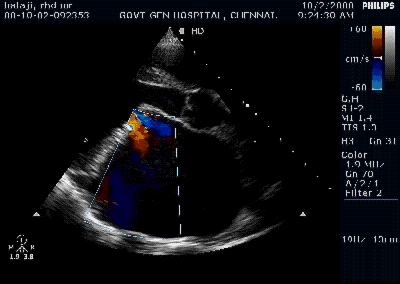

Pericardial effusion is often detected in patients with Infective endocarditis. Incidence can be as high as 25% . Most often it is mild, can be moderate in few.

During the echocardiographic evaluation of IE, the presence of pericardial effusion should be specifically looked for. These patients should be flagged and will require monitoring as the prognosis of PE complicating IE is a concern unless proved benign.